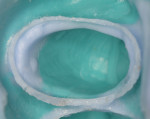

The insertion of two different retraction cords of different diameters, which are adapted to the variable morphology of the sulcus, is suggested. The first thinner cord, the compression cord (#000), is applied deep in the sulcus around each preparation with light pressure and without overlapping (Figure 1). The aim of this cord is to “seal” the sulcus and to avoid contamination of the margins by blood or crevicular fluid, and it is maintained in place during application of the impression material. This cord should be pre-moistened with water and squeezed to artificially reduce its volume to facilitate insertion and avoid tissue damage. If the cord is inserted dry, it will attach to the intrasulcular epithelium, and, if pulled back while packing, may cause bleeding.

The second wide-diameter cord, the deflection cord (most frequently #00), is then soaked in an astringent/hemostatic solution such as Hemodent (aluminum-chloride solution), Astringedent (aluminum-chloride gel), or Tissue Goo (aluminum-sulfate gel) and inserted in the entrance of the sulcus to achieve tissue displacement (Figure 2 and Figure 3). Again, these solutions act as a lubricant during cord placement. Both the first and second cords will expand after placement, causing a mechanical displacement of the soft tissue. Ideally, the cord should remain in place for about 5 minutes to achieve the optimum tissue displacement. The astringent or hemostatic agent will complement the retraction because transient ischemia shrinks the gingival tissue (Figure 4). Again, the hemostatic agent needs about 5 minutes to promote the chemical retraction of the soft tissue, which helps the dentist to achieve a perfect impression (Figure 5).

The selection of the second cord size is based on the depth of the sulcus and soft-tissue type. In general, when there is minimal sulcus depth, the clinician is limited in many cases to placing only a single cord. A thin and delicate gingiva needs to be treated with small retraction cords in order to avoid permanent retraction. A thick gingiva needs a larger-size cord in order to achieve best displacement. In general, the second cord needs to be visible after packing (Figure 4). If it “disappears” inside the sulcus, a larger size should be considered. The bottom line is that the second cord must be small enough to allow an atraumatic placement and large enough to promote a perfect impression with clear margins (Figure 5).